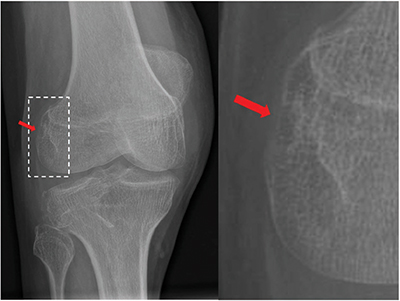

Figure 1

Radiography of the right knee demonstrating an erosion of the popliteal sulcus (red arrow).